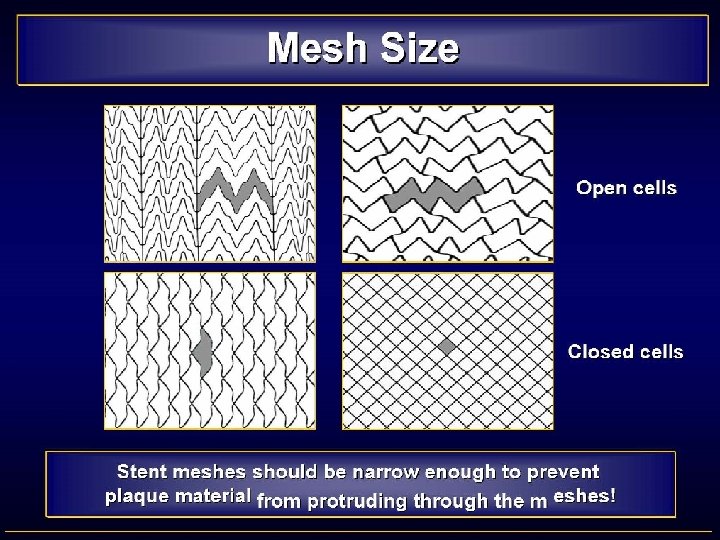

“Free cell area” based analysis ALL EVENTS Total Symptomatic Asymptomatic population n/N % < 2. 5 mm² 48/2107 2. 3% 20/882 2. 3% 28/1225 2. 3% 2. 5 -5 mm² 3/135 2. 2% 1/52 1. 9% 2/83 2. 4% 5 -7. 5 mm² 16/327 4. 9% 10/155 6. 5% 6/172 3. 5% > 7. 5 mm² 23/610 3. 8% 17/228 7. 5% 6/382 1. 6% TOTAL 90/3179 2. 8% 48/1317 3. 6% 42/1862 2. 6%

“Free cell area” based analysis LATE EVENTS Total Symptomatic Asymptomatic population n/N % < 2. 5 mm² 26/2107 1. 2% 11/882 1. 2% 15/1225 1. 2% 2. 5 -5 mm² 3/135 2. 2% 1/52 1. 9% 2/83 2. 4% 5 -7. 5 mm² 11/327 3. 4% 8/155 5. 2% 3/172 1. 7% > 7. 5 mm² 21/610 3. 4% 16/228 7. 0% 5/382 1. 3% TOTAL 61/3179 1. 9% 36/1317 2. 7% 25/1862 1. 3%

“Free cell area” based analysi. S Late events: Total population Free cell area Odds Ratio 95% C. I. 2. 5 -5 vs. < 2. 5 mm² 1. 869 [0. 557 -6. 267] 5 -7. 5 vs. < 2. 5 mm² 2. 681 [1. 310 -5. 490] > 7. 5 vs. < 2. 5 mm² 2. 963 [1. 653 -5. 313]

“Free cell area” based analysi. S Late events: Symptomatic population Free cell area Odds Ratio 95% C. I. 2. 5 -5 vs. < 2. 5 mm² 1. 553 [0. 197 -12. 261] 5 -7. 5 vs. < 2. 5 mm² 4. 309 [1. 705 -10. 893] > 7. 5 vs. < 2. 5 mm² 5. 976 [2. 733 -13. 065]

“Free cell area” based analysi. S Late events: Asymptomatic population Free cell area Odds Ratio 95% C. I. 2. 5 -5 vs. < 2. 5 mm² 1. 992 [0. 448 -8. 860] 5 -7. 5 vs. < 2. 5 mm² 1. 432 [0. 410 -4. 998] > 7. 5 vs. < 2. 5 mm² 1. 070 [0. 386 -2. 963]

Conclusion • Different complication rates between stents • Almost entirely explained by symptomatic population • Late complication event rates are – Highest for the open cell types – Increase with increasing free cell area • Prospective randomised trials required to further investigate the importance of free cell area • For the time being, stents with a small free cell area should be used in symptomatic patients

EMBOLIGENIC LESIONS • CONSIDERATIONS - Most emboli occur during stent-placement and postdilatation - 40% stroke after the procedure • STENTS REQUIREMENTS - Good wall coverage - Capturing of emboligenic material - Avoid plaque protrusion • CHOICE Closed-cell design